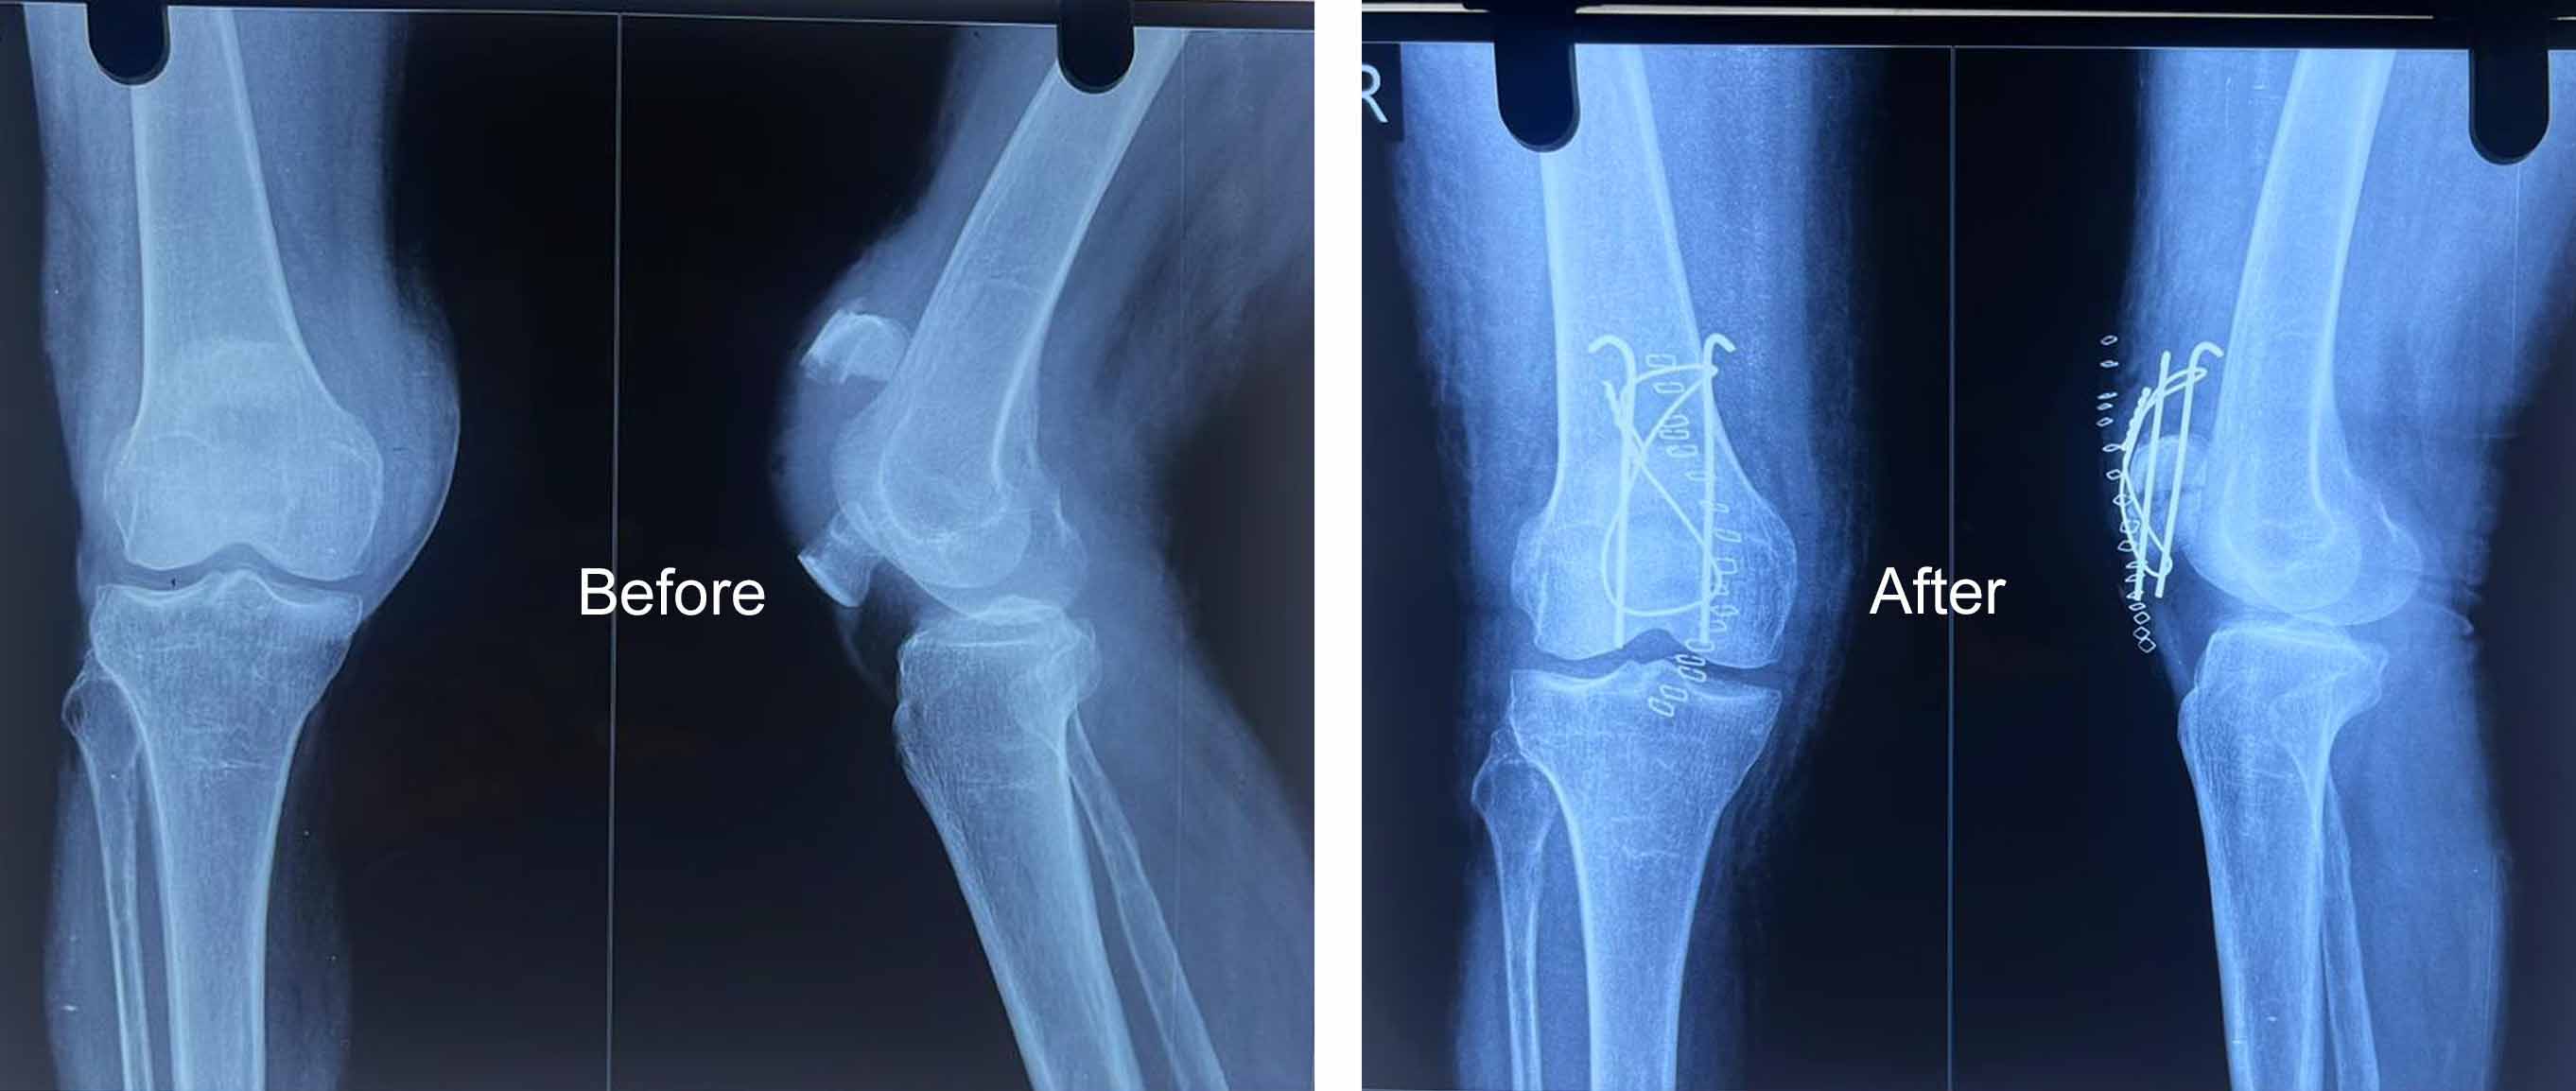

Dr Muhammed Riyadh is a distinguished medical professional in the field of orthopedics, has made significant contributions to the healthcare industry through a career marked by expertise, compassion, and unwavering dedication to patient well-being

Gallery